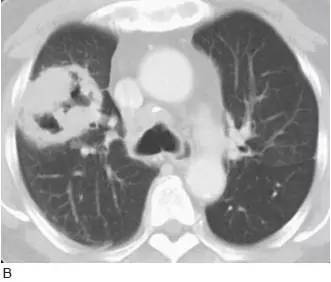

图7 弥漫性细支气管肺泡癌

A. 胸片显示右肺基底部的实变( 箭头);

B.5mm 层厚的CT 显示多个区域的实变,含有空气支气管征,多发的边界不清的结节,这些结节呈小叶中央分布,代表气腔或腺泡结节,在弥漫性细支气管肺泡癌中很常见